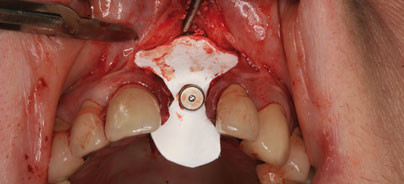

Nach der Extraktion des Zahnes 21 zeigt sich nach Mobilisation eines bukkalen Gingiva-Periostlappens eine große Dehiszenz der bukkalen Knochenlamelle (Abb. 1).  Am Periost sind noch Reste von Granulationsgewebe erkennbar (Abb. 2). Bei der Mobilisation des bukkalen Gingiva-Periostlappens wird auf Erhaltung der Papillen geachtet. In palatinaler Angulation wird mit dem Finalbohrer eine Knochenkavität präpariert (Abb. 3). Knochenspäne werden aufgefangen und mit dem mit Blut vernetzten Bio-Oss® vermengt. Das Implantat wird primärstabil eingeschraubt (Abb. 4). Das Implantat wird an der vestibulären Dehiszenz mit einem Gemisch aus Knochenspänen und mit Blut benetztem Knochenersatzmaterial großzügig abgedeckt (Abb. 5)